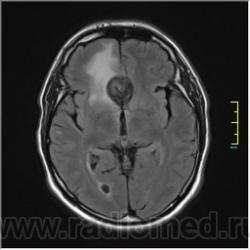

Post-GAD:

Иначе говоря, аневризма с хронической геморрагией, т.к. мы видим фракции крови различного возраста.

Постепенное пристеночное образование тромбов приводит к появлению типичного для аневризмы феномена -слоистости МР сигнала в полости аневризмы. Данная картина демонстрирует слоистый характер тромботических масс в полости аневризмы .Функционрирующая часть имеет низкий сигнал во всех режимах сканирования. Дополнительно-перифокальный отек.

А может более корректно интерпретировать как частично тромбированная аневризма... Уж коь речь идет о фракциях, ну то есть о тромбе по сути.... Ну и плюс перфокальный отек головного мозга (вероятнее цитотоксический+вазогенный).